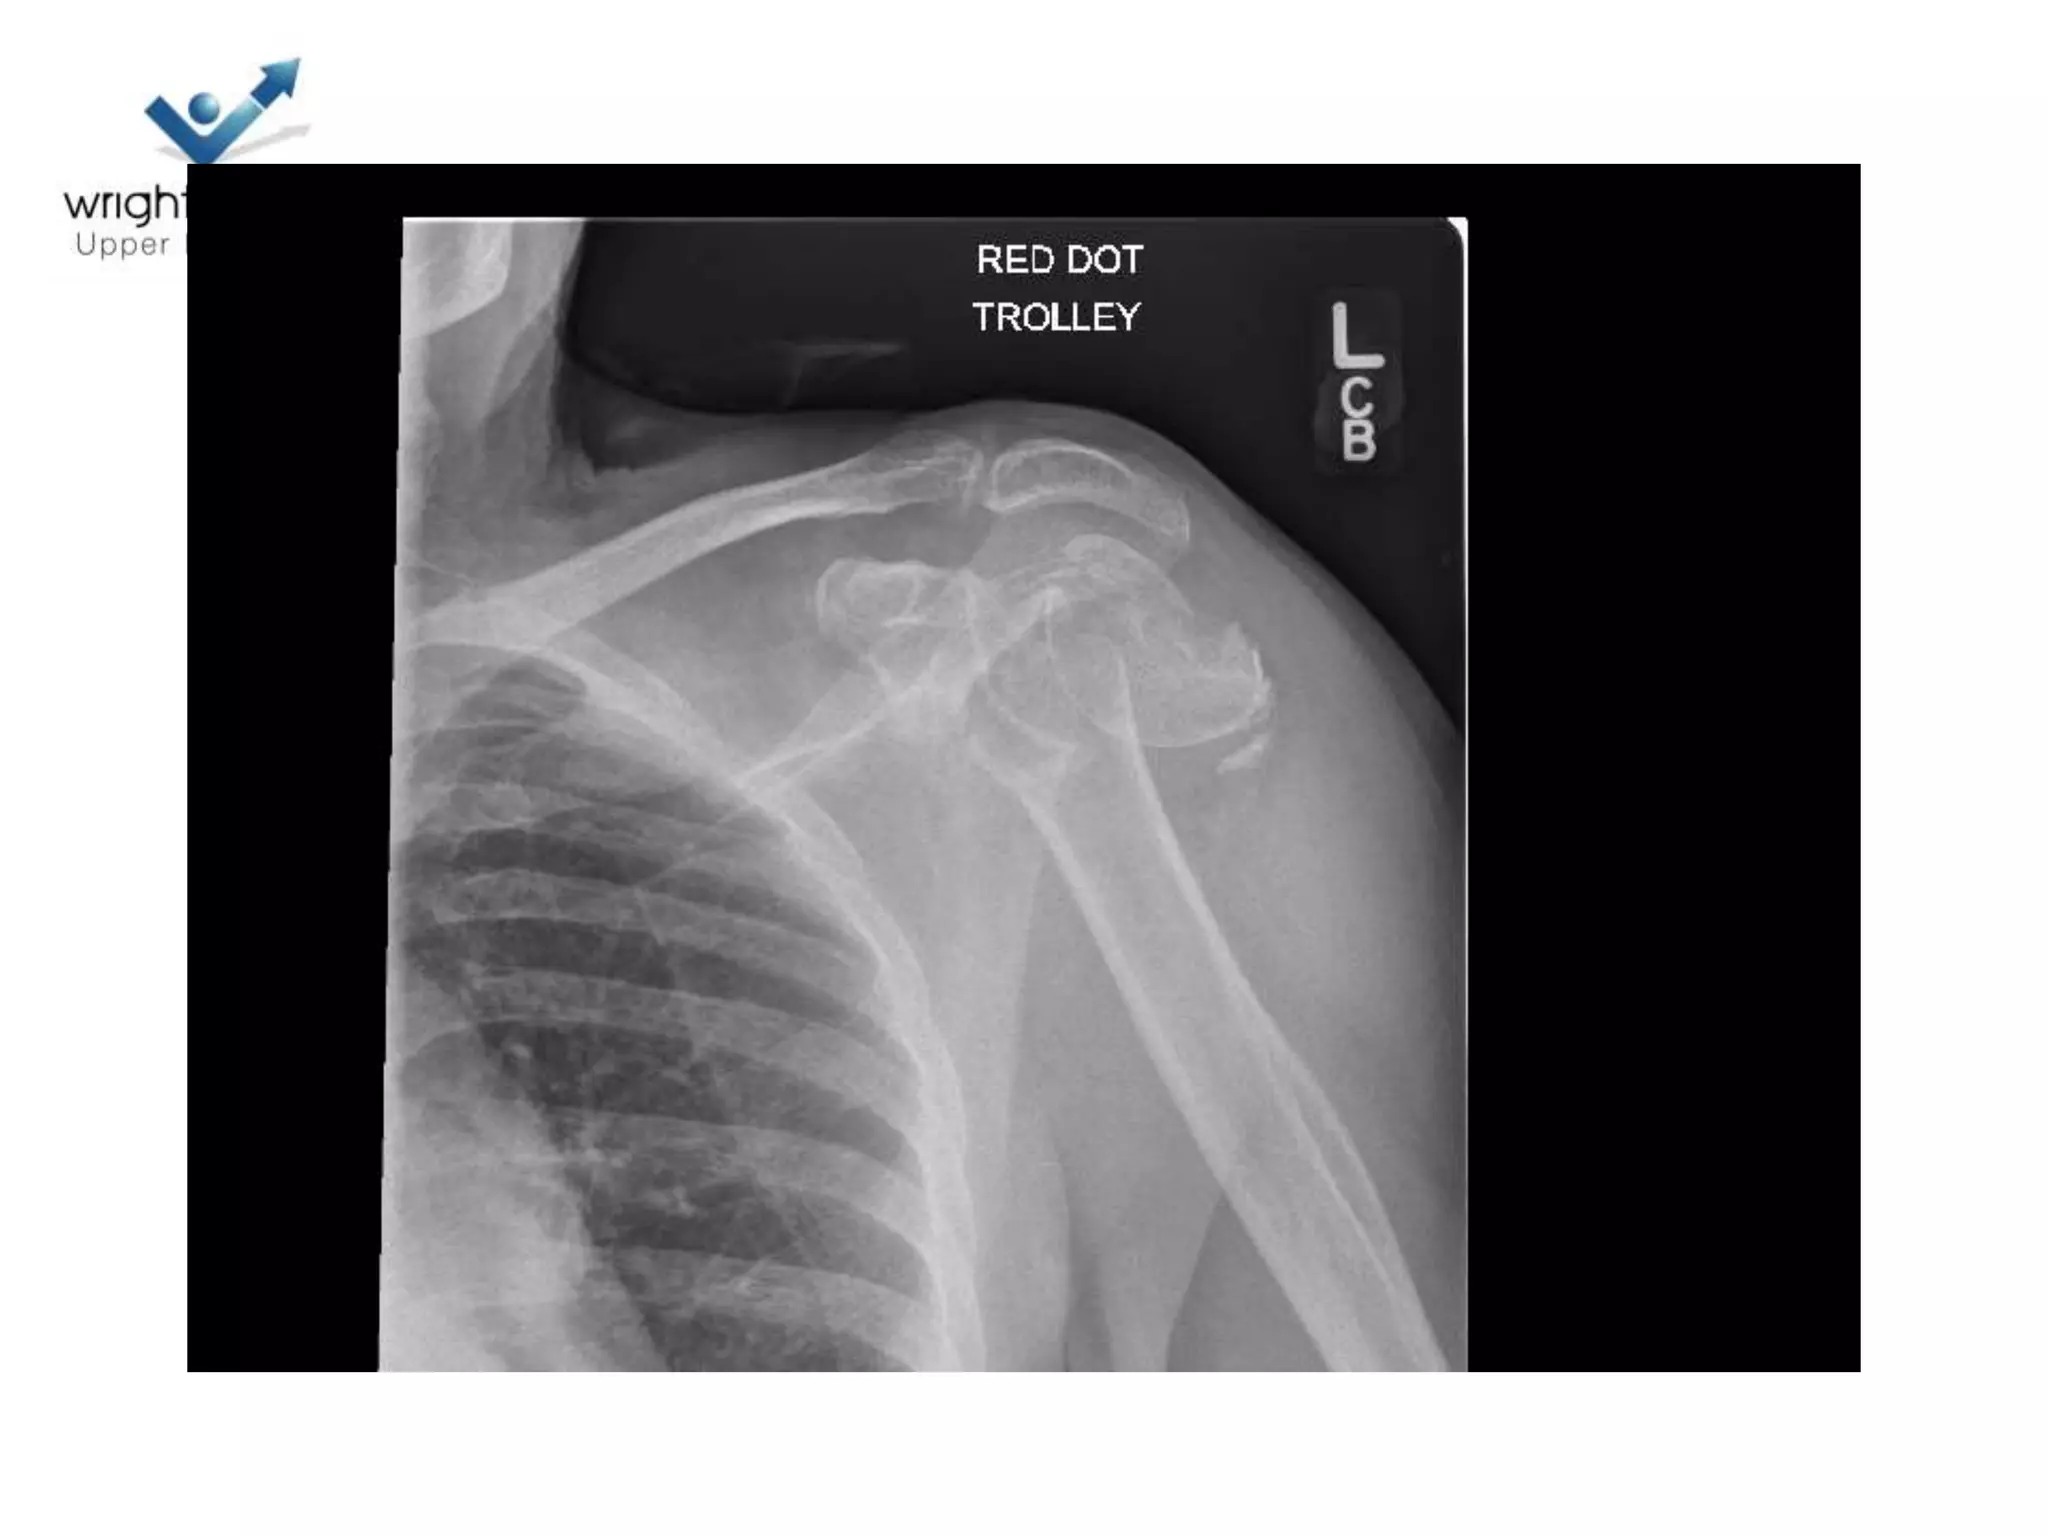

Case discussions

4 Next…